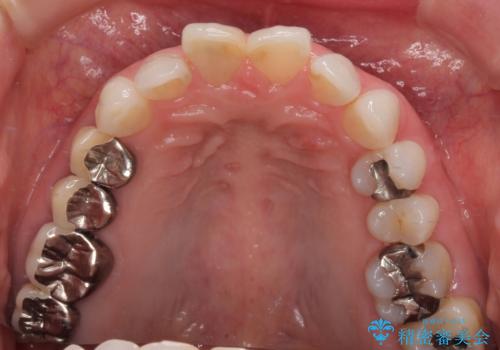

- 前歯の変色と、以前装着したクラウンが黄ばんできたことを気にして来院された患者様です。

前歯に変色が起こる場合、神経組織の失活により引き起こる可能性が高いため、診察を行ったところ、根尖部の病変や叩いたときの痛みなどが認められました。

まずは根管治療を行い、痛みの消退を確認してからオールセラミッククラウンによる補綴治療を行うこととしました。

黄ばんできてしまった小臼歯部のクラウンは、根尖部に症状を認めないため、そのままオールセラミッククラウンによる補綴治療を行うこととしました。